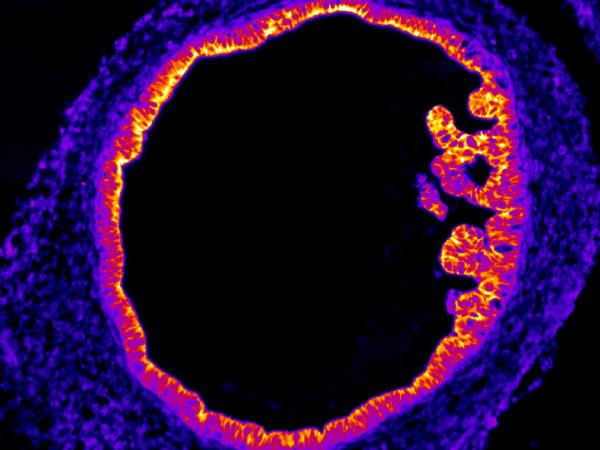

HIO/Intestin ©MMahé Blastocyste ©LDavid Mésothélium ©CBlanquart Rhéomètre ©PF Bio3

Les organoïdes sont des modèles cellulaires intermédiaires entre les cultures cellulaires en monocouche et les modèles in vivo. Ils sont développés grâce aux progrès des dernières décennies en termes de culture et de différenciation des cellules souches, ainsi que de culture en 3D. Ces modèles tri-dimensionnels présentent l’avantage d’être produits à partir des cellules de la même espèce, contrairement aux modèles animaux. Les utiliser permet ainsi de se rapprocher des conditions physiologiques et/ou physiopathologiques pour incrémenter la connaissance du fonctionnement tissulaire en présence ou non de molécules extérieures.